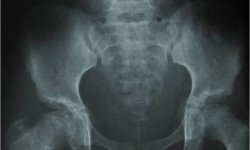

Multiple Epiphyseal Dysplasia

Fig 1: Pelvis AP with Hips